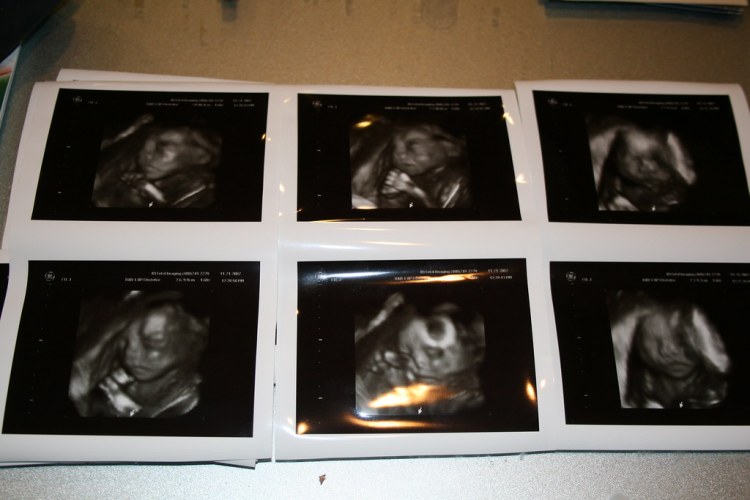

24 weeks - 3d ultrasound - jencu - FlickrEl embarazo es una de las experiencias más emocionantes de la vida de una persona, y la tecnología ha hecho posible que las futuras madres y padres puedan tener una mirada única y en tiempo real de su bebé en el vientre. Los ultrasonidos 4D son una forma avanzada de visualizar el desarrollo y la salud del feto, y ofrecen una experiencia emocionante para las madres y padres que buscan conectarse con su bebé antes de su nacimiento.

Los ultrasonidos 4D utilizan tecnología de imagen en tiempo real para producir imágenes en movimiento de un bebé en el vientre. Estas imágenes no solo muestran el aspecto físico del bebé, sino que también permiten ver su movimiento y su comportamiento. Esto puede ser especialmente útil para monitorear el desarrollo y la salud del bebé, y para detectar cualquier posible problema de manera temprana.

Desde una perspectiva emocional, los ultrasonidos 4D son una forma única de conectarse con el bebé antes de su nacimiento. Las futuras madres y padres pueden ver el rostro, las manos y los pies de su bebé, y verlo moverse y hacer muecas. Esto puede fortalecer el vínculo entre la madre y el bebé, y prepararlos para su llegada. Además, los ultrasonidos 4D son una forma excelente de compartir la alegría y la emoción del embarazo con la familia y amigos, lo que puede hacer que la experiencia sea aún más especial e inolvidable.